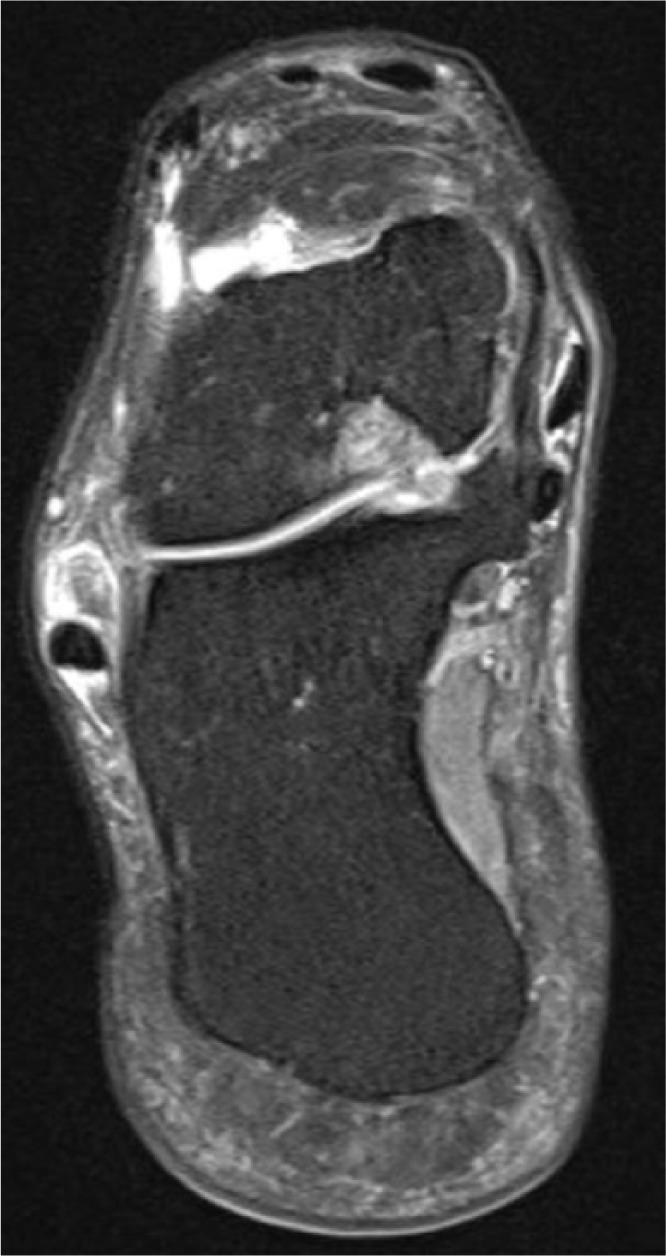

We reviewed and analysed this patient's records containing the sport-specific anamnesis, pre-existing condition, anamnesis of medications and therapy. The three injuries were magnetic resonance imaging-proven. Furthermore, the tendon's condition was examined histologically in the context of the operative treatment through lace technique of the Achilles tendon and transfer of the peroneus brevis to the peroneus longus. We also researched the literature for bilateral ruptures of the peroneal tendons.

我们回顾并分析了该患者的记录,包括运动专项病史、既往病史、用药史和治疗情况。这三处损伤均经磁共振成像证实。此外,在通过跟腱编织技术和将腓骨短肌转移至腓骨长肌进行手术治疗的过程中,对肌腱状况进行了组织学检查。我们还在文献中搜索了腓骨肌腱双侧断裂的病例。